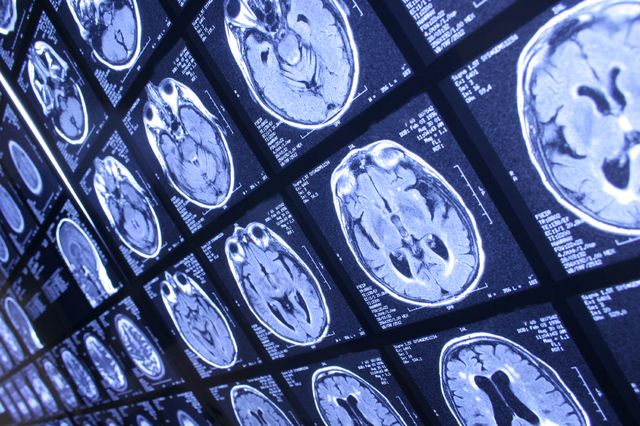

For the current study, Bearden, who is part of the UCLA Semel Institute for Neuroscience and Human Behavior, conducted MRI scans of 143 study participants: 66 with 22q deletions, 21 with 22q duplications, and 56 without the genetic mutation.

Those in the group with 22q deletion, which carries the risk for schizophrenia, had thicker gray matter, but less brain surface area — a measure which relates to how folded the brain is — compared to those in the duplication group. The people in the 22q duplication group, who at risk for autism, had the opposite pattern, with thinner gray matter and larger brain surface area.